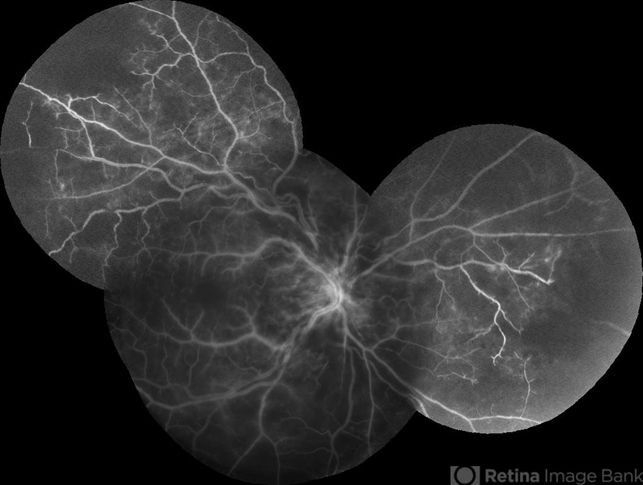

- central retinal vein occlusion (CRVO)

- Fundus camera

- Fundus photograph of a 75-year-old woman with hypertension and dyslipidemia who presented to the clinic with sudden decrease in vision on her right eye.